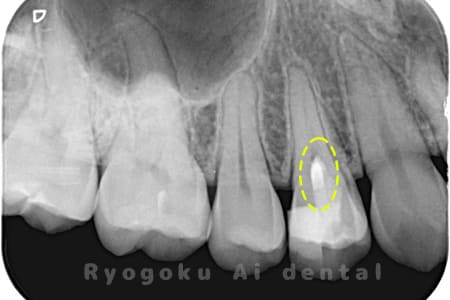

Case03

-

- 原因

- むし歯

- 治療期間

- 補綴装着期間を含めて3回

- 治療内容

- 断髄治療

- 治療費用

- 66,000円

違和感があるとのことでレントゲン撮影を行なったところ、プラスチックの被せ物の中で虫歯が広がっていると判断。レントゲンの状態からも神経にかなり近いため、患者様と相談し、断髄治療を行なったケースです。3年間のフォローアップ期間中で現在トラブルはなし。

<リスク・副作用>

術後は痛み、腫れ、痺れなどの副作用が生じる場合があります。症状が再発する可能性があります。その場合は抜髄する必要があります。